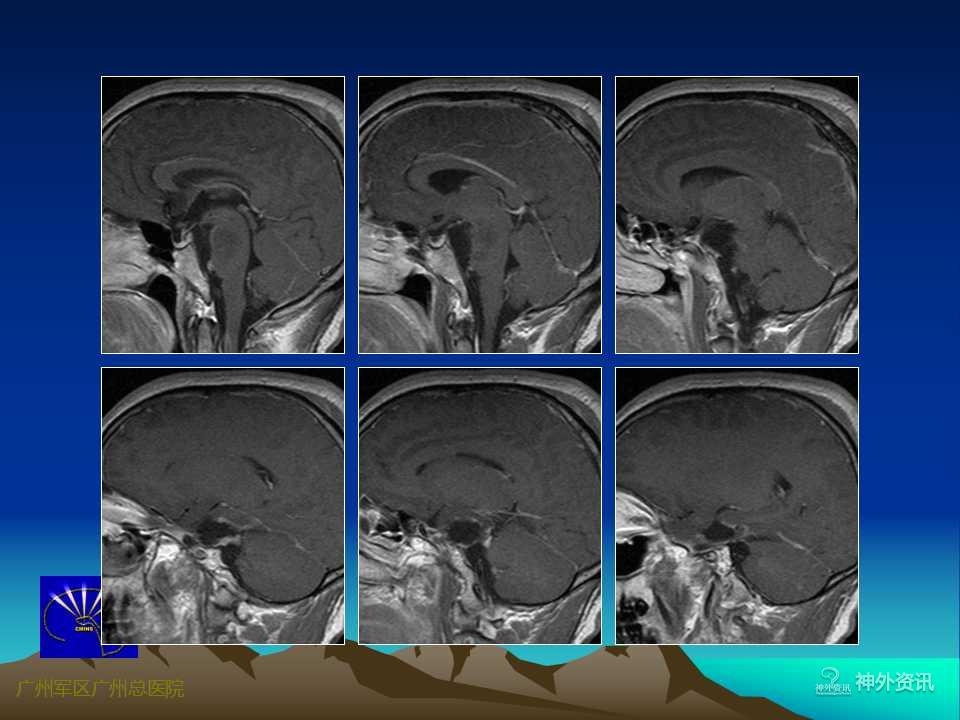

岩尖区是指从内听道到岩骨尖的这一狭小区域,毗邻海绵窦后壁,有岩上窦和岩下窦汇入,后方为脑干(中脑和脑桥)、基底动脉及其分支,邻近有Ⅲ~Ⅷ脑神经走行。岩尖区肿瘤常骑跨中、后颅窝及幕上、下两个颅区,与上述重要解剖结构紧密相邻或相连,手术难度较大,术后并发症相对较多。随着显微神经外科技术的不断发展和对该区域显微解剖结构认识的不断提高,目前该区域肿瘤手术的死亡和致残率已明显下降,但仍被认为是当前神经外科极具挑战性的手术之一。

岩尖区肿瘤以脑膜瘤最为常见,其次为神经鞘瘤、胆脂瘤等,由于脑膜瘤基底较宽,与其周围结构粘连较紧,故手术难度最大,且肿瘤是否侵及海绵窦是决定手术能否全切及影响手术预后的一个重要因素。岩尖区肿瘤的手术入路有多种,主要根据肿瘤的主体部位、侵及方向、供血特点以及毗邻结构等。可选择的手术入路有:经颅底岩斜区前方入路、侧方入路、后方入路、或幕上下联合入路等。

岩尖区肿瘤的手术入路较多,不同的手术入路有其各自的适用范围和不足之处。术前详尽的神经影像学检查对术前整体评估至关重要。将CT、CTA(含肿瘤组织、颅骨与血管的三维重建)、MRI、MRA等影像资料结合起来进行综合评判,充分了解肿瘤周围的解剖结构,特别是肿瘤的血供特点、与重要血管神经(脑神经)和脑干等的相互关系。DSA检查可明确肿瘤供血及周围血管移位情况。3D打印的出现使术者能够在3D打印模型上详细了解肿瘤的具体部位、大小、形态,肿瘤与其周围血管、脑干、脑神经、颅底等的相互关系,对指导手术入路、手术策略等具有极其重要的意义。随着人们对生活理念的改变,生存质量已备受重视。因此,目前对颅底肿瘤的手术已朝着简单、低侵袭性的方向发展,不再过分强调肿瘤的全切率,在保留重要神经血管功能的前提下最大限度地安全切除肿瘤、保证术后生活质量已成为广大神经外科医生和患者考虑的首要问题。